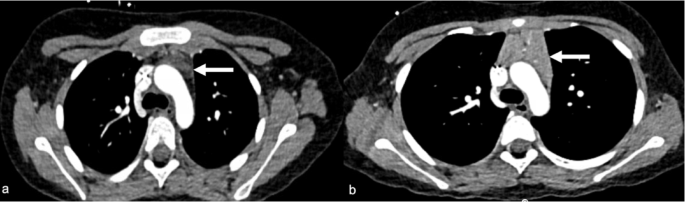

All chest CTs were reviewed by a pediatric radiologist with 8 years of experience (I.V.), who divided the patients into two groups according to the thymus size: Group 1 demonstrated a visual increase in thymus size after CAR T-cell therapy (Figs. 3 and 4). Group 2 demonstrated no change in thymus size or decreased size (i.e., no increase in thymus size) (Fig. 5). Then CT images were imported into OsiriX (Pixmeo, Bernex, Switzerland) and the thymus was outlined using the free-hand drawing tool. Automated 3D volume rendering was used to derive the volume (cm3) of the thymus (Fig s1). In addition, the same radiologist recorded the presence of lung, pleural, and mediastinal abnormalities. To complement this analysis, fluoroscopy images from interventional radiology (IR) procedures for peripherally inserted central catheter (PICC) line placement were reviewed when available. These IR fluoroscopic images, acquired at clinically relevant time points between the available chest CT and CAR T-cell infusion, provided additional reference for mediastinal silhouette and thymus size assessment. Specifically, the transverse thymic diameter was measured on these fluoroscopic chest images, allowing for comparison of thymic width before and after CAR T-cell therapy.

Axial chest computed tomography (CT) images of a 9-year-old male patient with B-ALL pre- and post-CAR T-cell therapy. a) An axial chest CT image pre-CAR T-cell therapy shows the initial size and shape of the thymus. The thymus presents as triangular tissue in the anterior mediastinal region and does not cause any mass effect on adjacent vessels. b) An Axial chest CT image at 53 days post-CAR T-cell therapy shows an enlarged and more lobulated thymus. The thymus has increased in size (from 0.55cm3to 73.51cm3) and exhibits a lobulated shape with sharp, rounded margins and increased contrast enhancement.